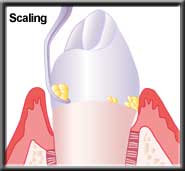

Scaling removes plaque & calculus |